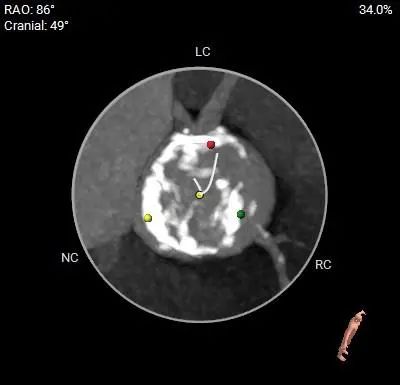

跨瓣角度为LAO 3° CAU 4°(右窦中心位),球囊预后扩角度为LAO 14° CRA 8°(左冠切线位);

瓣膜释放角度推荐RAO 28° CAU 31°(左右重合位),推荐瓣环上0-2mm开始定位释放。